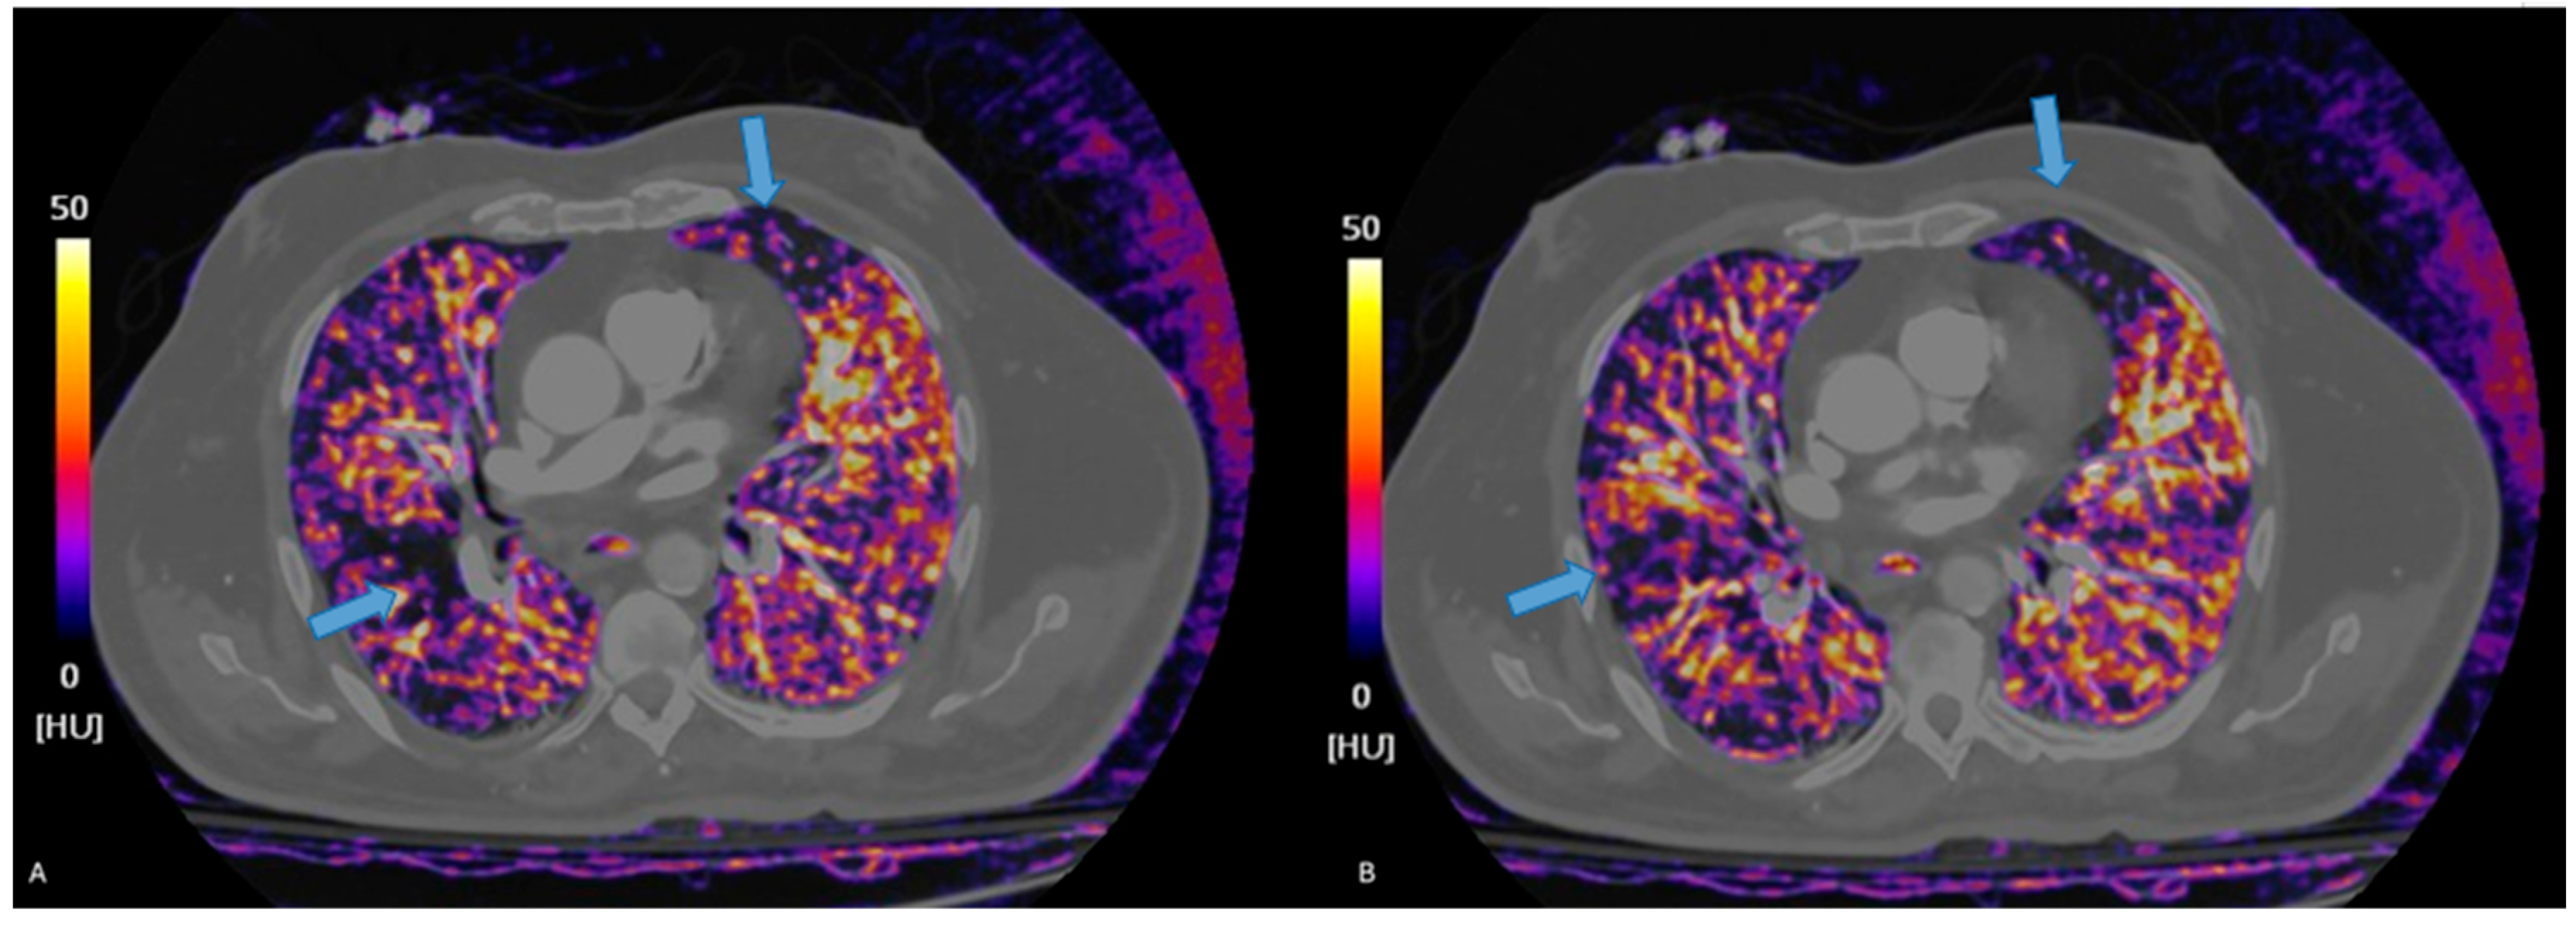

3.2. Dual Energy CT

3.2.1. Principles of DECT

3.2.2. Accuracy of DECT

3.3. Photon-Counting CT

3.3.1. Principles of Photon Counting